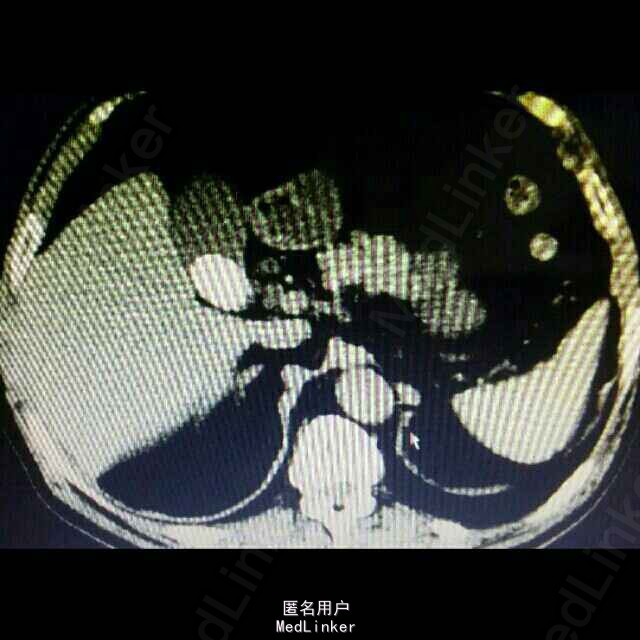

1、 主诉:上腹部疼痛4年余,加重2月。 2、 现病史:患者4年前无明显诱因出现上腹间歇性胀痛,可忍受,伴反酸、恶心、无呕吐,未予以治疗。患者2月前上腹部通天症状加重,伴肩部放射痛,伴反酸、恶心、无呕吐,未予以治疗。患者15天前因“感冒”就诊于当地医院行胸部CT示:肝左叶胆管结石并肝内胆管扩张、肝左叶萎缩。今患者为进一步治疗,前来我院就诊,门诊以“胆囊结石并急性胆囊炎”收入院,患者自发病以来精神状态可、食欲差,睡眠良好,大、小便正常,体重无明显变化。

3、 辅助检查:上腹部 CT平扫示:肝左叶胆管结石并肝内胆管扩张、肝左叶萎缩。胆囊结石,双肾囊肿。